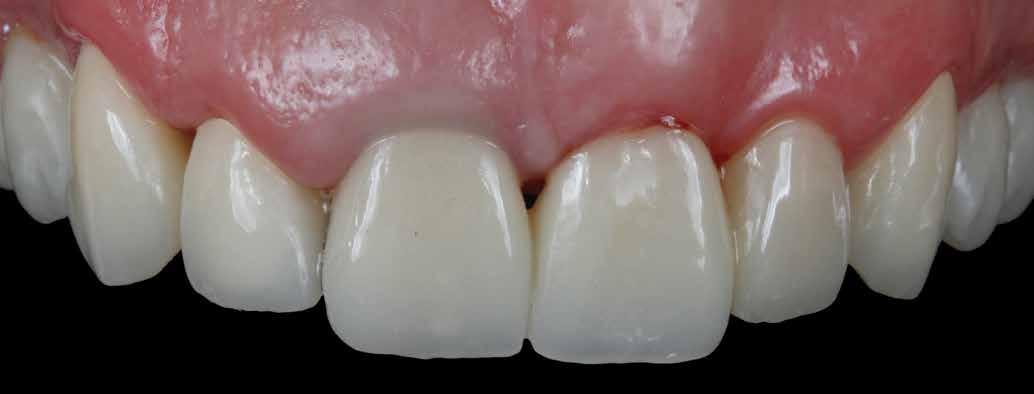

A szakirodalomban fellelhető eredmények alapján kerámia héjak ragasztására a kontaminációtól mentes, frissen vágott zománc felszín a legalkalmasabb. A hosszú távú sikeresség elérésének további feltétele a fogak konzervatív módon történő preparálása, továbbá a ragasztás kofferdám felhelyezésével biztosított, abszolút izolálásban történő kivitelezése. Úgy véljük, hogy a fenti faktorok biztosították a cikkben bemutatásra kerülő esetek – 5 évvel az átadás után megfigyelhető – sikerességét. A kofferdám izolálás alkalmazása számos előnyt biztosít a gyakorló fogorvos számára. Megakadályozza a munkaterület nyállal, vérrel, vagy szulkusz-váladékkal történő kontaminációját, és javítja a kezelendő területre való rálátásunkat. A fogak kerámia héjak ragasztása előtt történő izolálása azonban gyakran kihívást jelenthet a kevesebb klinikai tapasztalattal rendelkező fogorvosok számára. Jelen esetbemutatásban ismertetjük a kofferdám felhelyezésének lépéseit és néhány olyan gyakorlati tanácsot, amelyek jelentősen megkönnyíthetik a munkánkat, azokban az esetekben, amikor a második kisőrlőfogak közti területet kívánjuk kofferdám segítségével izolálni. A kofferdám kapcsok segítségével került rögzítésre, majd fogakat körülvevő széleit óvatosan az ínybarázdába forgattuk. A kerámia héjak számára előkészített fogakra ragasztás előtt egyenként kapcsokat helyeztünk annak érdekében, hogy a kerámia héjak rögzítése ideális körülmények között történhessen. A lépések részletes ismertetése segítséget jelenthet – a kevesebb klinikai tapasztalattal rendelkező fogorvosok számára – az abszolút izolálás megvalósításához szükséges lágyrészmenedzsment megértéséhez. Ezek az ismeretek rendkívül hasznosak lehetnek, ha a jövőben a kerámia héjak ragasztását megfelelő módon megvalósított kofferdám izolálás mellett kívánják kivitelezni. A cikkben ismertetett módszerek alkalmazásával az abszolút izolálás megvalósítható, a gumilepedő – vérzés nélkül – ínybarázdába történő beforgatására, és a ragasztáshoz szükséges idő csökkentésére.

Az oxigén inhibíciós réteg kialakulásának elkerülése érdekében a kerámiafelszíneket glicerin géllel (Liquid Strip, Ivoclar Vivadent, Schaan, Liechtenstein) borítottuk, majd ezeket a felszíneket ismét 20-20 másodpercen keresztül világítottuk. A végeredmény megfelelt a páciens esztétikai igényeinek (6. a. ábra). Az átadott restaurátumok épségének megőrzése érdekében, a páciens számára éjszakai fogvédő sín készült. Az ötéves kontroll alkalmával megállapítottuk, hogy az elvégzett kezelésünk továbbra is sikeresnek tekinthető (6. b. ábra)

Az általunk alkalmazott adhezív rendszerek hatékonyságát nagymértékben növelhetjük azáltal, hogy a fogakat minimál invazív módon, azaz csak zománcon belül preparáljuk, és a kerámia héjakat kofferdám izolálásban ragasztjuk. Jelen esetismertetésünknek az volt a célja, hogy bemutassuk, hogyan lehet az adekvát módon kivitelezett kofferdám izolálással megelőzni

a munkaterület nyállal, vérrel vagy szulkusz-váladékkal történő kontaminációját. A megfelelő méretben kialakított perforációs nyílások és köztük lévő optimális távolság elengedhetetlen ahhoz, hogy a kofferdámot ideális módon tudjuk felhelyezni. Ezzel az esettel azt is bizonyítjuk, hogy a gumilepedő levegőfújással, fogselyemmel és teflonszalagok segítségével történő beforgatásával az ínyvérzés kialakulását el lehet kerülni. Ismételten szeretnénk hangsúlyozni, hogy a megfelelő kofferdám kapcsok használata nélkül nem tudtuk volna a preparált csonkszélt a gumilepedő szélétől eltartani. A kezelés során elért eredményeket jól alátámasztotta, hogy a páciens az ötéves kontroll vizsgálat során teljesen elégedett volt.